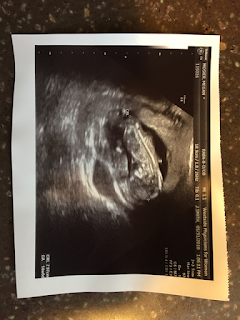

- April 19th: We had our second appointment and got to see baby again on ultrasound! This time he/she was more developed - we saw a head, arms, and body very clearly and got to hear the heartbeat! Baby was very active so the doctor commented it was hard to get a good picture on the ultrasound! They adjusted our due date to December 1st, 2018.

| 8 week ultrasound |